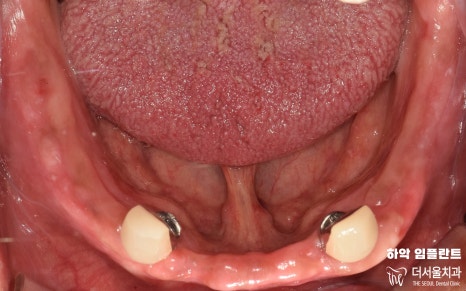

부분틀니에 필요한 최소 개수 식립와

크라운 세팅까지 잘 마무리 되었습니다.

이제 남은 것은 부분틀니 제작 및 착용이죠?

해당 진료 역시 보험 적용을

받을 수 있는 부분이라

비용 부담을 덜어낼 수 있어

환자분 마음의 짐을 조금이나마

가볍게 해드릴 수 있습니다.